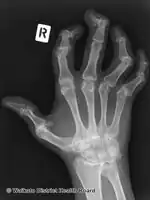

Nail changes

Psoriasis can affect the nails and produces a variety of changes in the appearance of finger and toe nails. Nail psoriasis occurs in 40–45% of people with psoriasis affecting the skin and has a lifetime incidence of 80–90% in those with psoriatic arthritis.[30] These changes include pitting of the nails (pinhead-sized depressions in the nail is seen in 70% with nail psoriasis), whitening of the nail, small areas of bleeding from capillaries under the nail, yellow-reddish discoloration of the nails known as the oil drop or salmon spot, dryness, thickening of the skin under the nail (subungual hyperkeratosis), loosening and separation of the nail (onycholysis), and crumbling of the nail.[30]